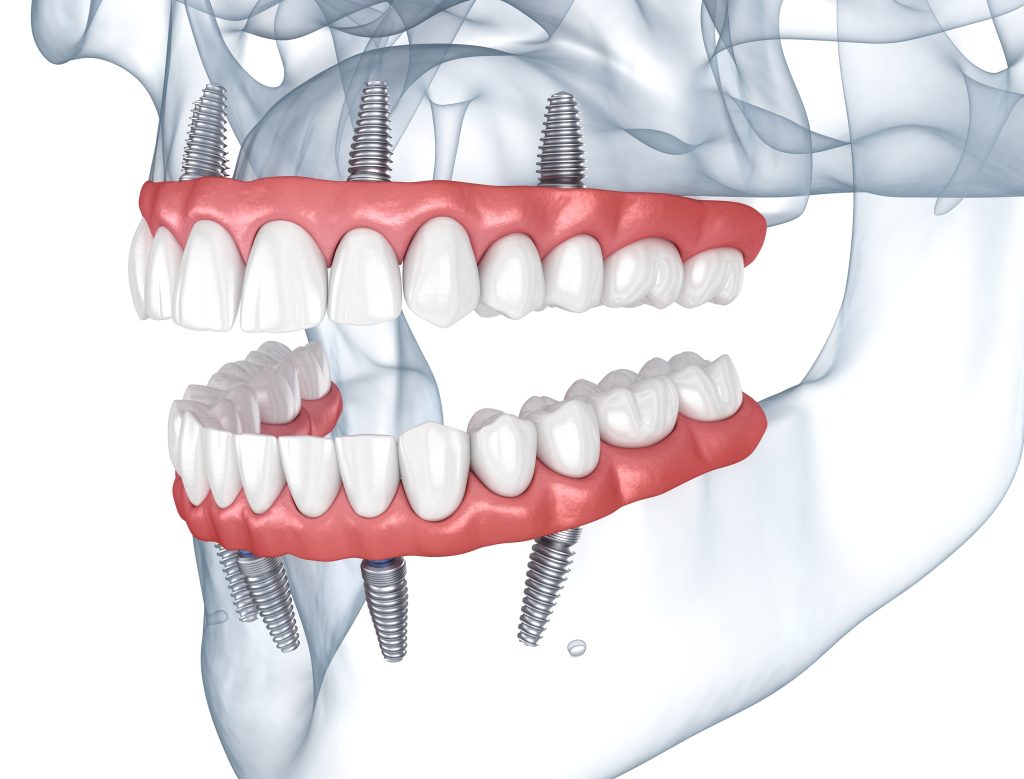

This streamlined approach involves placing only four dental implants per jaw to secure an entire arch of replacement teeth firmly in place. The result is a fixed prosthetic that functions like natural teeth, enabling efficient chewing and clear speech while looking completely authentic. Most remarkably, patients receive functional teeth immediately after implant placement, transforming smiles and lives in a single day.

On procedure day, you receive appropriate anesthesia, ranging from local numbing to sedation options that keep you comfortable and relaxed throughout treatment. Dental surgeons then place four implants per jaw using the precisely planned positions determined during your evaluation phase.

In cases where jawbone volume has diminished, surgeons angle certain implants strategically to engage the densest available bone while avoiding critical structures like sinus cavities and nerve pathways. This angled placement technique enables successful All-on-4 treatment even for patients with significant bone loss, frequently eliminating bone grafting requirements and reducing treatment complexity substantially.

The complete implant placement surgery requires approximately two hours, depending on case difficulty and individual anatomy. At Thailand Dental Implant Center, fully digital protocols enhance efficiency, speed, and precision throughout the procedure. After placing all implants, surgeons verify their stability and carefully close surgical sites, preparing for the exciting next phase.